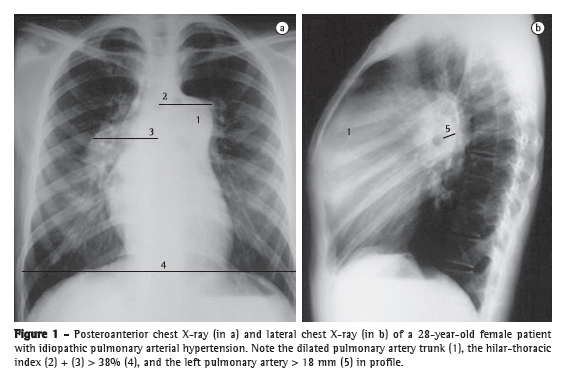

However, RV ejection fraction and volumes cannot be calculated with the use of the mathematical equations usually employed to study the LV. Therefore, several echocardiographic parameters have been developed to assess RV function and the hemodynamics of the pulmonary artery. The most widely used of those methods is based on the identification of tricuspid regurgitation (TR). Measurement of TR provides an estimate of the pressure gradient in the right heart. The first studies involving continuous wave Doppler echocardiography were published in the mid-1980s.(9,10) The technique consists of measuring peak velocity of tricuspid regurgitation (VTR), which provides an estimate of the regurgitant flow from the RV to the right atrium (RA), as shown in Figure 3. With the use of the simplified Bernoulli equation (∆P = 4 × VTR2), it is possible to convert the flow measurement into an estimate of pressure. By adding this pressure gradient and an estimate of RA pressure, we obtain RV peak systolic pressure (RVSP), an approximation of the pulmonary artery systolic pressure (PASP), provided that there is no obstruction of the RV outflow tract. An RVSP > 35-40 mmHg is suggestive of PH.(10) In the presence of low regurgitant flow, the estimation of RVSP becomes less sensitive, because of the low signal intensity, which might lead to the underestimation of pressure values. However, the presence of extremely severe TR might also lead to the underestimation of pressure measurements, because equalizes the RA and RV pressures, resulting in a weak Doppler signal. Conversely, the method might also overestimate RVSP values.

Other echocardiographic parameters can also be used in the evaluation of PH. Measurement of TR at the opening of the pulmonary valve is used for estimating pulmonary artery diastolic pressure (PADP).(15) It is also possible to estimate pulmonary vascular resistance, which correlates with invasive hemodynamic measurement.(16) Atrial contraction and the subsequent increase in intracavitary pressure result in the formation of a characteristic wave, known as the A-wave. A less pronounced or absent A-wave on the PAP curve, probably attributable to increased PADP, is highly suggestive of PH. However, in patients with RV dysfunction, a normal A-wave does not rule out PH. Measurement the acceleration time of the pulmonary artery flow also has good accuracy in detecting increased PAP, representing an estimate of the mean pulmonary artery pressure (mPAP).(17) In addition, the finding of an increased RV systolic time interval is a highly specific echocardiographic sign of PH, albeit one with low sensitivity.(16) Other echocardiographic signs, such as right heart enlargement, pericardial effusion, RV dysfunction, paradoxical interventricular septal motion, and reduced LV filling volumes, also corroborate the presence of PH (Figure 3).(18) Provided that their limitations are taken into account and that they are evaluated and interpreted in the light of the clinical context, all these parameters can be useful in the diagnosis and follow-up of patients with PH.